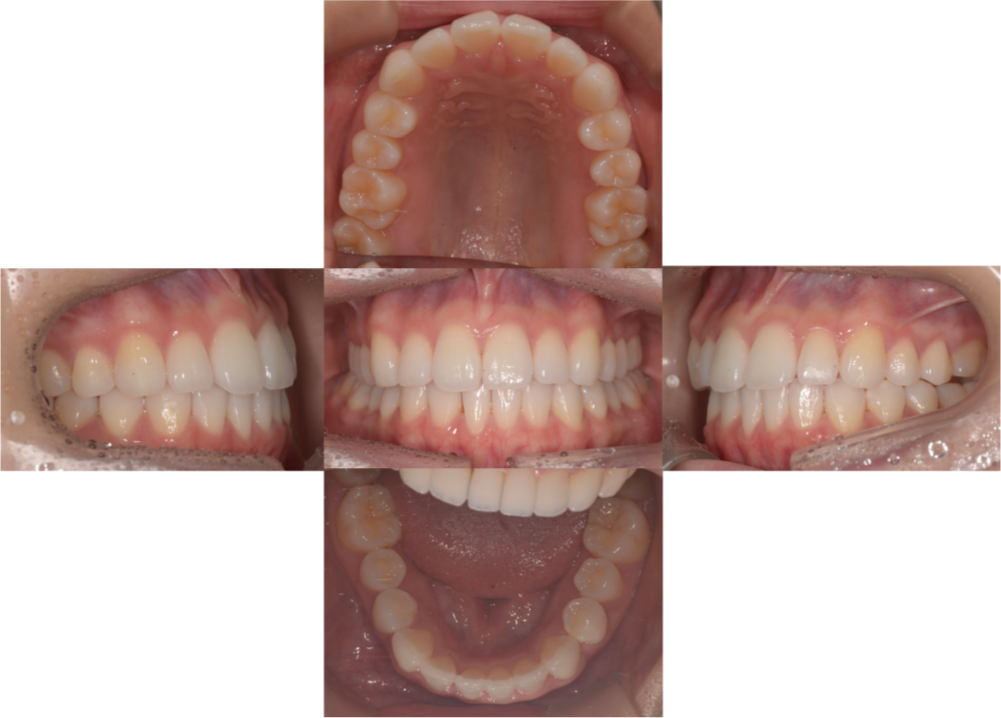

初診時

動的治療終了時

Before・after

| 主訴 | 前歯2本が出ている |

|---|---|

| 矯正装置 | インビザラインシステム、エラスティックゴム、リンガルボタン(クリア) |

| 初診時年齢 | 23歳 |

| 診断 | 上顎前歯唇側傾斜を伴う両側AngleClass1、SkeletalClass1 |

| 抜歯の有無 | 非抜歯 |

| 来院頻度 | 4〜8週に1回 |

| 治療期間 | 23ヶ月(1年11ヶ月) |

| 費用の目安 | 80万円程度 |

| リスク | ・装置が擦れて唇や頬に口内炎ができることがある ・マウスピース装着時間を遵守しないと治療効果が得られない可能性がある ・スクリューアンカー埋入時、多少の疼痛が生じることがある ・歯根吸収を誘発する可能性がある |